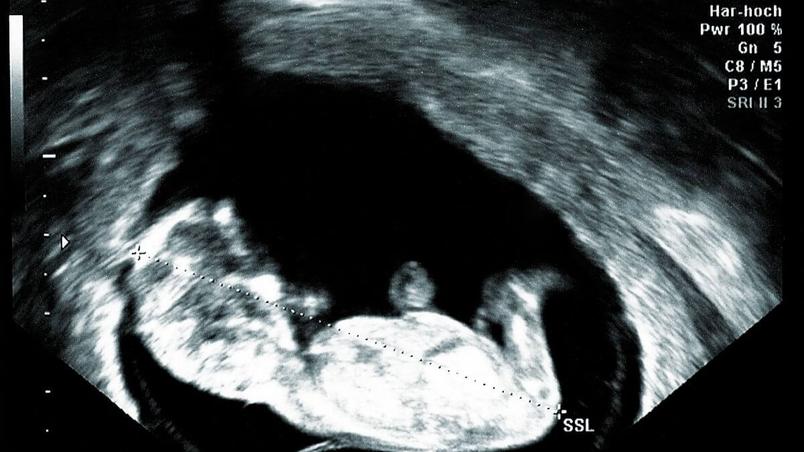

Well, typical 12 week ultrasound pictures are a sea of black and white and gray. Within that sea, you should be able to make out some mini legs, a mini spine, a mini face (often with a mini nose bone), and a mini body.

In the 12-week sonogram, you’ll also be able to see your placenta and how your blood is moving around inside you to ensure the process all goes smoothly.

You’ll also likely get a beautiful snapshot to go up on your fridge – that’s one of the best things about 12-week ultrasound pictures!

With options for a 3D or 4D 12-week ultrasound and even a standard 12-week sonogram, you’ll have ample opportunity to see baby. But what exactly can you expect to see?

Well, at 12 weeks, your fetus will be about about the size of a lime or that adorable plum we mentioned. Which is exactly where the similarities with fruit ends.

You’ll be pleased to know that by week 12, your baby will start to look a little more ‘human’, but they’ve still got a long way to go with growing!

Yes, although they’ll be teeny-tiny, baby’s limbs will be formed, along with their nervous system, circulation, and organs. Baby’s face will also be taking shape and their bone structure will be set.